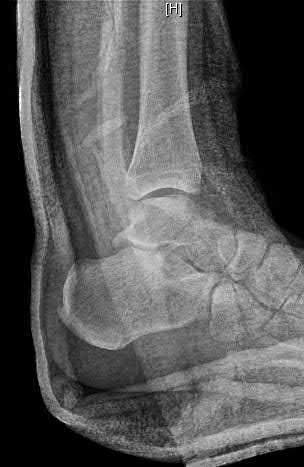

Figures A and B are the Lateral and AP radiographs of a displaced talar neck fracture with tibiotalar dislocation. Figures C and D are the post-reduction sagittal foot CT cuts that reveal a displaced talar neck fracture with medial

comminution.

The patient has sustained a displaced talar neck fracture with medial comminution which requires open reduction and internal fixation to restore anatomic alignment. The patient has likely sustained varus malunion which is a common deformity noted with non-anatomical reduction leading to hindfoot supination and decreased eversion.

Talar neck fractures, while uncommon, can lead to significant morbidity in the ambulatory patient. Treatment of these injuries requires prompt reduction due to the tenuous blood supply to the talus. The most common complications noted after a talar neck fracture are avascular necrosis, subtalar arthritis, tibiotalar arthritis, and varus malunion. A talus varus malunion generally occurs due to medial talar neck comminution and/or non-anatomic reduction of the injury. This deformity can lead to decreased eversion and a supination deformity causing patients to ambulate on the lateral aspect of the foot. These malunions are generally treated with a medial opening wedge osteotomy.